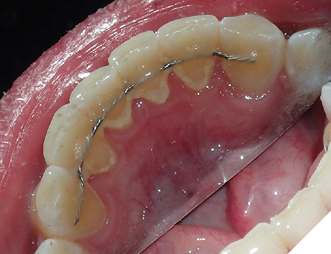

4. Bonded permanent retainer (Fig. 11AB)

Checking for:

i. smooth edges

ii. intact wire

iii. sufficient composite resin amount on bonded teeth

iv. showing good stability when checked with a hand instrument

Fig. 11A

Fig. 11B

Fig. 11C

Fig. 11D